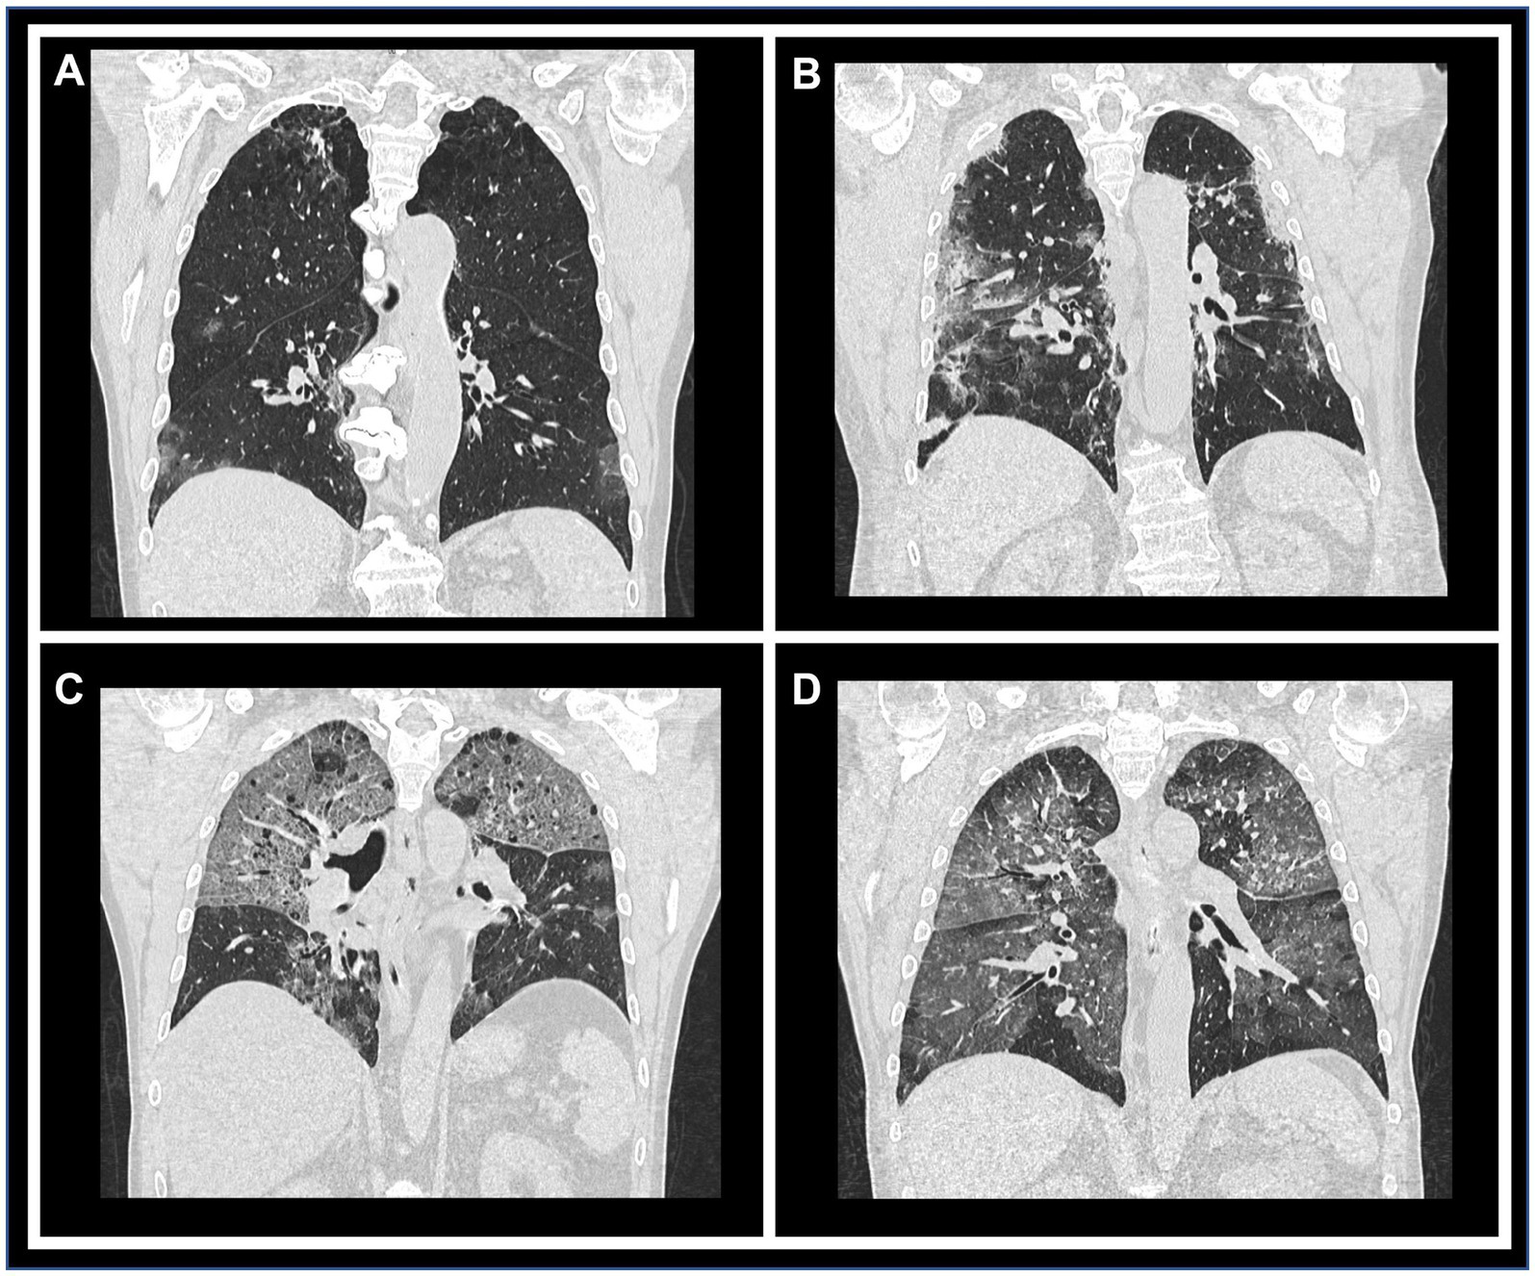

Figure 2. Representative CT images illustrating each qualitative/semi-quantitative scoring category. Coronal reconstructions of chest CT scans demonstrating varying degrees of parenchymal involvement. Panels (A) through (D) correspond to scores of 1 (10–25% involvement), 2 (26–50%), 3 (51–75%), and 4 (>76%), respectively, highlighting the progressive extent of lung impairment.